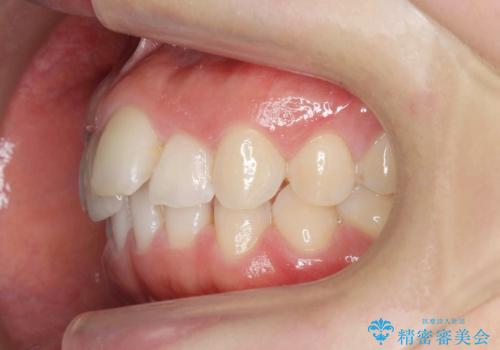

出っ歯に見える前歯の改善 部分ワイヤーとマウスピース矯正

- 出っ歯に見える前歯の改善を希望され、来院されました。

マウスピースでは改善の難しい歯の動きを部分ワイヤー矯正で整えたのち、奥歯の噛み合わせや細かい歯の並びをマウスピース矯正インビザラインで整えていきます。

最終的な前歯の並びに大変満足いただくことができました。